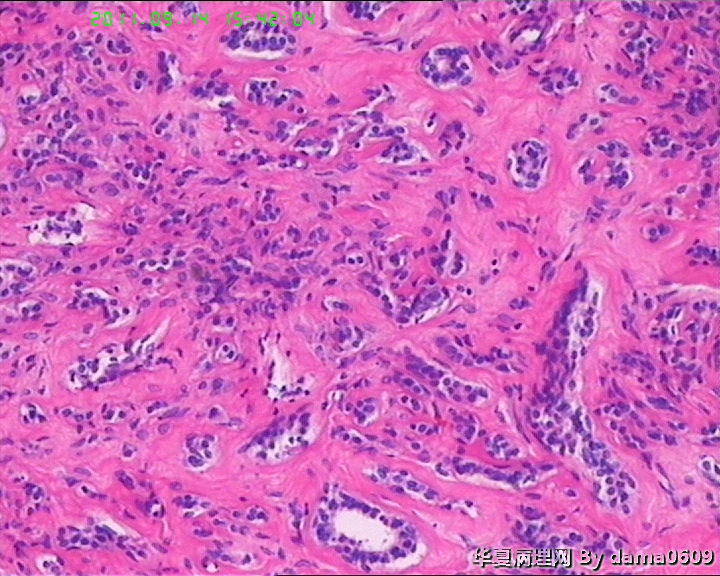

女,22岁,乳腺肿物,病史不详。

不整形软组织肿物一个,V:2.0x1.5x1.5cm。无包膜。切面实性,灰白色,小结节状,质中。

镜下结构复杂,图3、4、8、10、11、12、13、15、17、18、19、20为肿物中央区域,占标本大部分,图1、2、7、14为肿物边缘部分,图5、6、9、16、21为二者交界处。有点乱,不好意思,请老师别介意。

请教老师,诊断:硬化性腺病,可以吗??谢谢!!